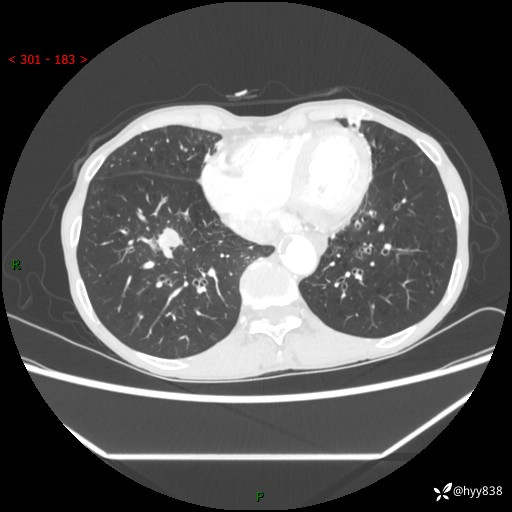

【现病史及既往史】:患者3天余前因既往肺气肿复查胸部CT发现“右肺下叶结节、双肺多发结节、双肺门及纵膈淋巴结增大”,平素偶有咳白色粘液痰,下肢乏力,无明显低热、盗汗、咯血、胸痛、喘气等不适,今为求明显结节性质遂来我院门诊就诊,门诊以“孤立性肺结节”收治入院。 起病以来,患者精神饮食睡眠一般,大小便正常,体力无明细变化,体重近年来较前下降。

【检查】:胸部CT增强